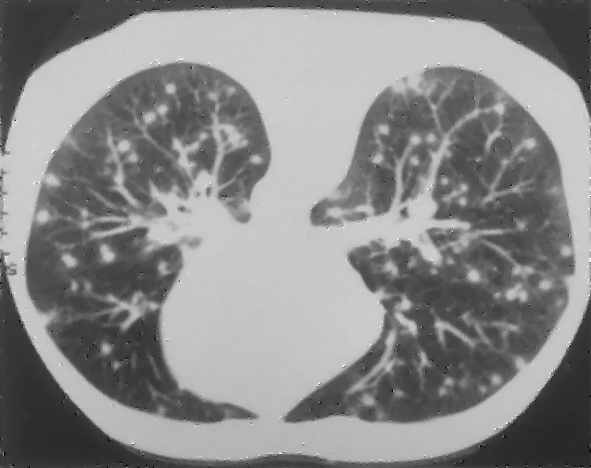

Example 2: restoration of images corrupted by blur and SPN or AWLN. In this example we evaluate the performance of the proposed TV-L1 model on three medical test images lungs (), Fig. 5 (a), ecography (), Fig. 6 (a), and aneurism (), Fig. 7 (a), synthetically corrupted by Gaussian blur of parameters band=5 and sigma=1 and by two types of impulsive noise, namely SPN and AWLN.

| (a) original | (b) TV-L1 (ISNR = 22.13) | (c) zoom of (b) |

![]() |

| (d) corrupted | (e) TVp-L1 (ISNR = 23.15) | (f) zoom of (e) |

| (g) -map () | (h) TV-L1 (ISNR = 25.46) | (i) zoom of (h) |

| (l) -map () | (m) TV-L1 (ISNR = 28.01) | (n) zoom of (m) |

First, for what concerns corruptions by SPN, in Figs. 5, 6, 7 we report for the three considered test images the original and corrupted image together with the estimated -maps in the first column (with the size of the neighborhoods used for the -maps estimation reported in the captions), the restoration results, obtained by the four compared methods, in the second column (with the achieved ISNR values in the captions) and a zoomed detail of the restored images - green- bordered in Figs. 5 (a), 6 (a), 7 (a) - in the last column.

The reported ISNR values as well as the visual inspection of the restored images and of the zoomed details strongly indicate how the proposed space-variant regularizer allows for higher quality restorations. In particular, it is worth remarking how, with respect to the space-variant TV model, the additional degrees of freedom represented by the scale parameters used in our proposal, yield a sufficient additional flexibility for avoiding unwanted spurious effects - see, e.g., spikes in Figs. 5 (i), 6 (i), 7 (i).